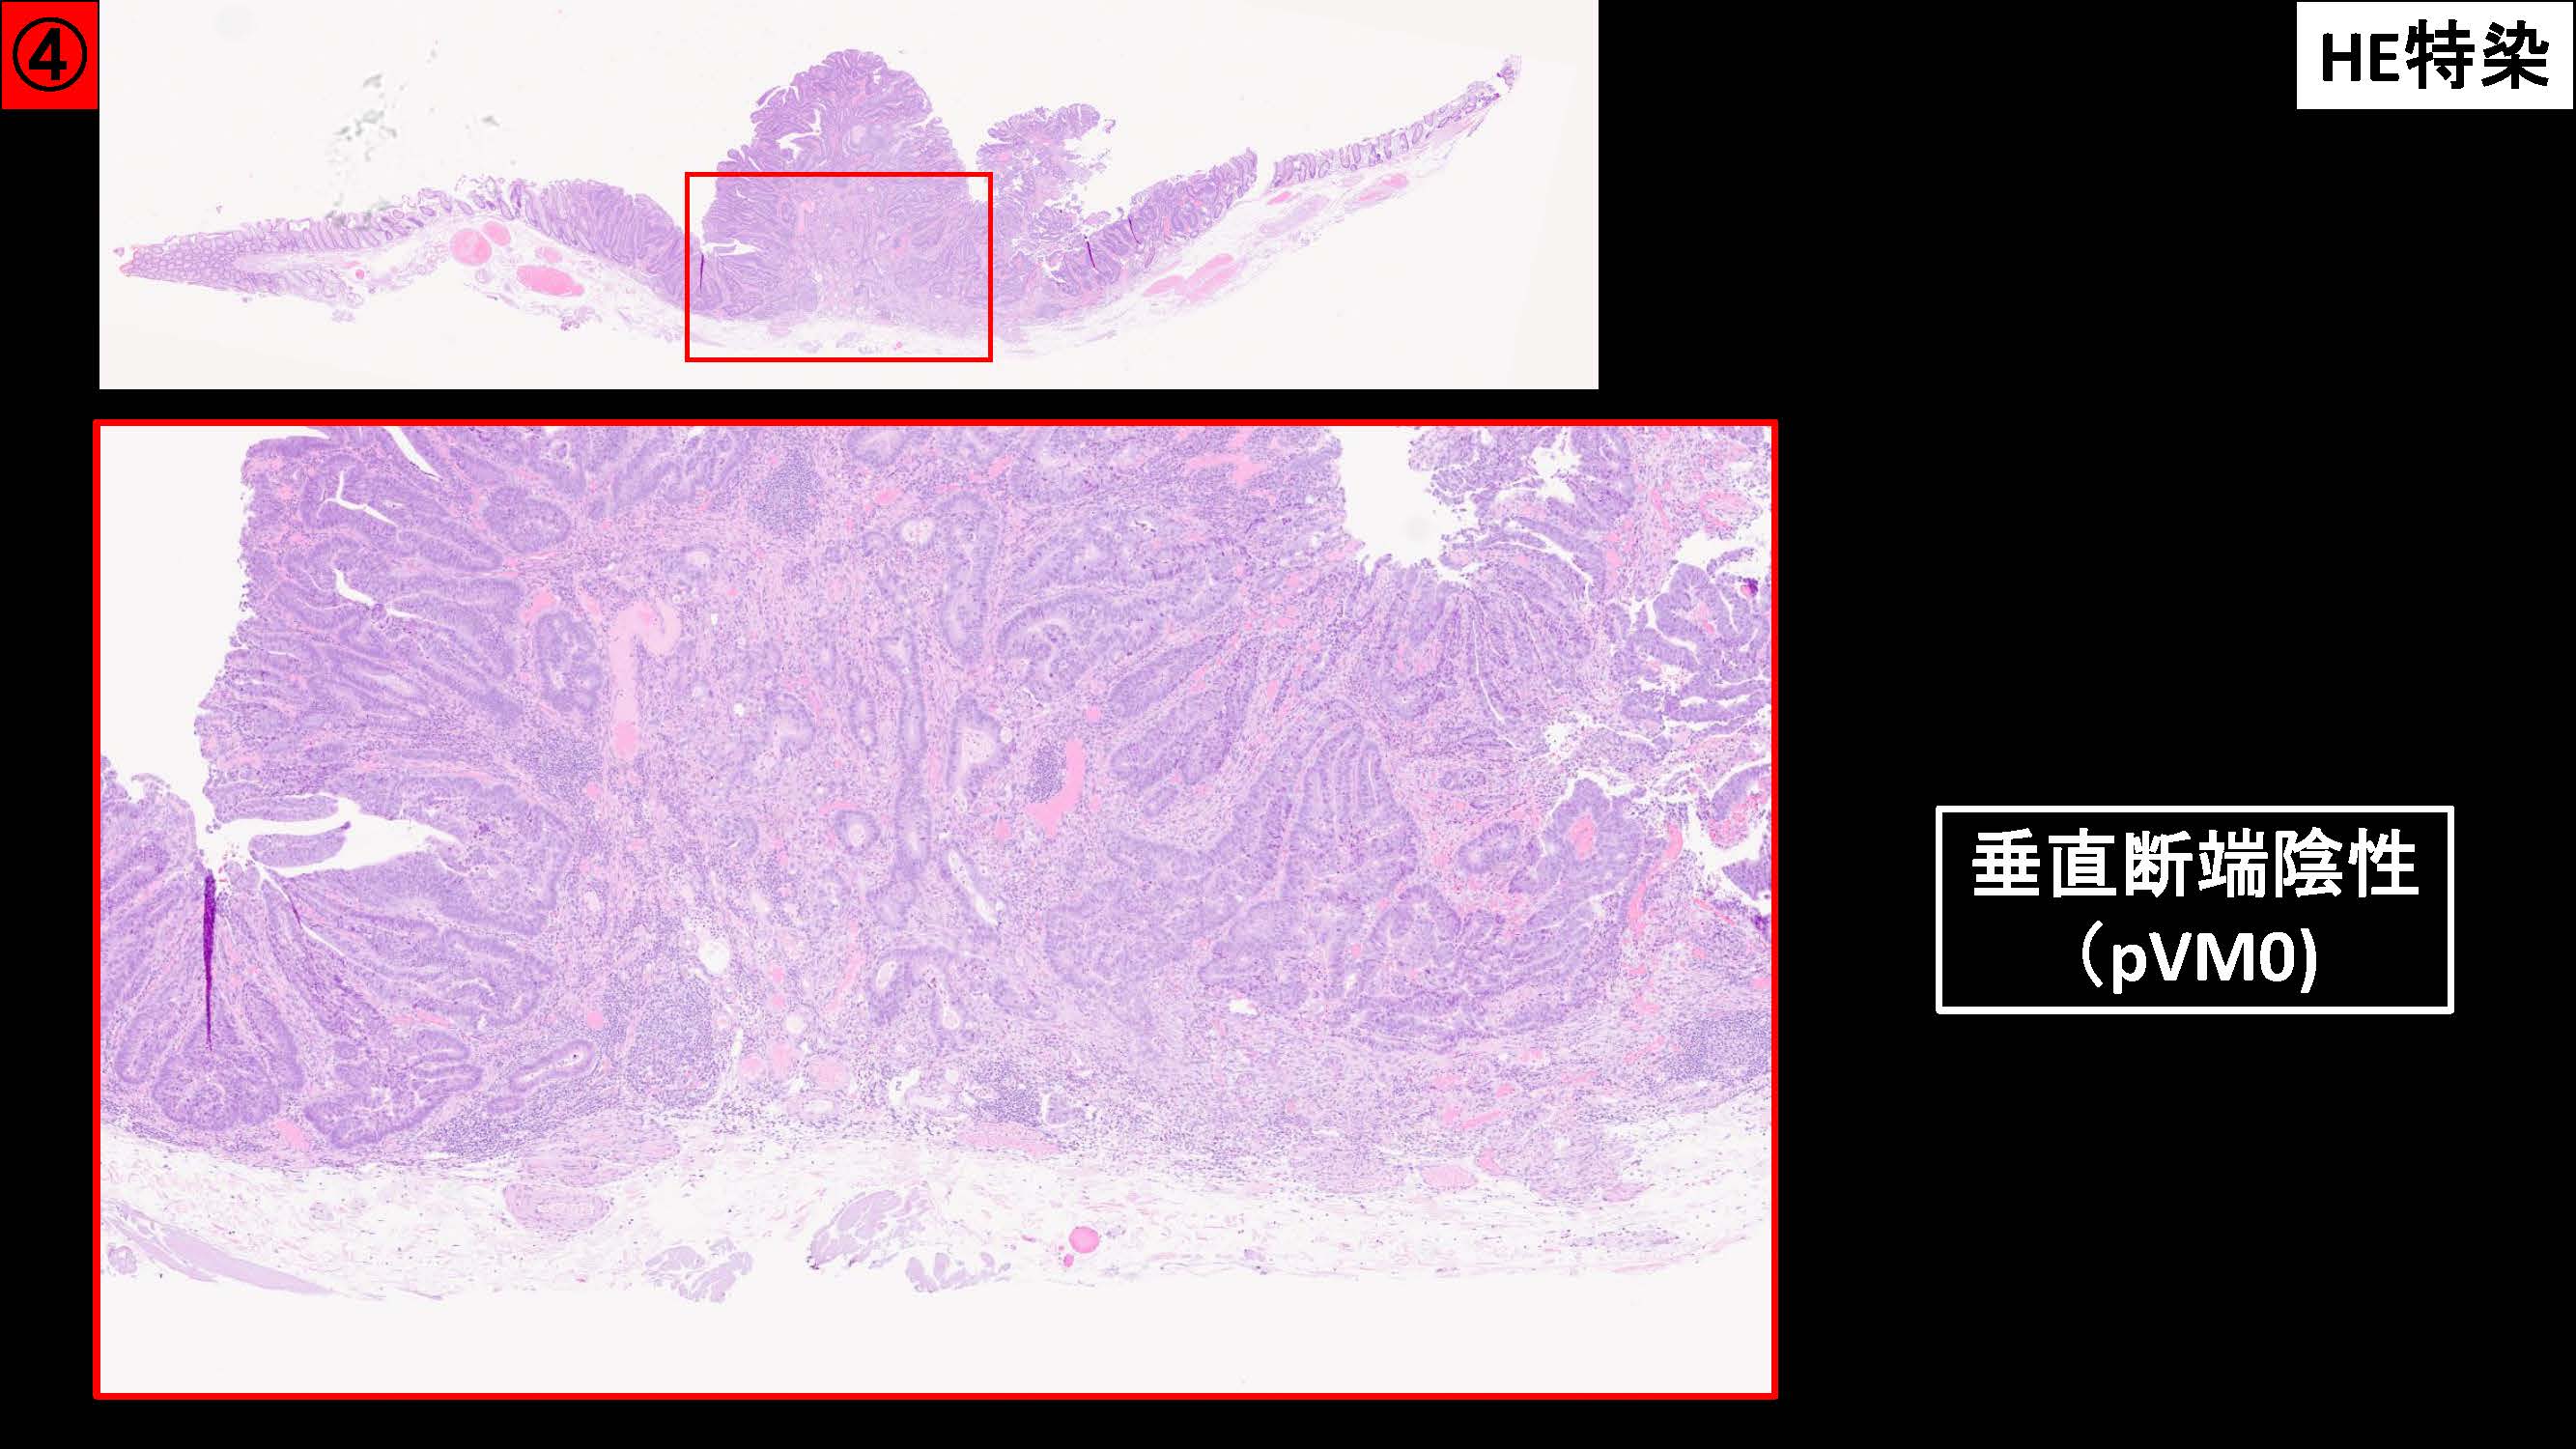

消化管Mapping~大腸~ 2025.6.11

消化管Mapping